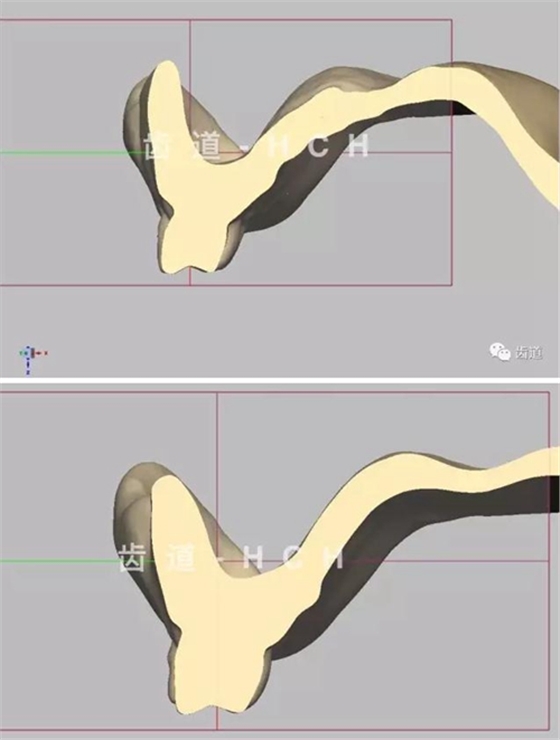

標(biāo)準(zhǔn)全口義齒模型截圖 科貿(mào)嘉友收錄